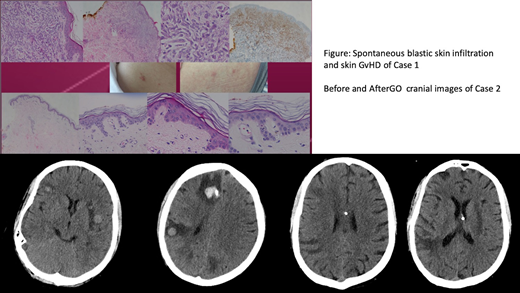

Our first case was a 40-years-old woman admitted to our outpatient clinic with pain in her joints and redness in her back and stomach. She was diagnosed with CD33-positive Acute Myeloid Leukemia according to the immunophenotyping of bone marrow blasts. Idarubicin and ARA-C (7+3) combination initiated as a frontline induction therapy and morphological remission was achieved after the first cycle of induction. After the first cycle of consolidation chemotherapy with high dose ARA-C she has relapsed with skin myeloid sarcomas and diffuse bone marrow infiltration. Soon after the relapsing disease she was put on to ida-flag salvage chemotherapy and she responded well with the disappearance of skin lesions and morphological complete remission of bone marrow. After achieving response, an allogeneic stem cell transplantation (HSCT) was applied from her sibling donor with a myeloablative conditioning. Unfortunately patient had a relapsing extramedullary disease with reappearance of skin lesions even with an ongoing acute skin gvhd (Figure) soon after allogeneic HSCT. Bone marrow biopsy revealed no increase in blast count.

We have decided to initiate a novel targetted therapy to control the extramedullary disease. As her blasts infiltrating the skin were universally CD 33 positive we considered to put her on GO therapy with the approval obtained from health authority. GO was applied according to the dosage approved by FDA for relapsing disease. After the first cycle of GO she had a rapid disappearance of all skin lesions just complicated with a febrile neutropenic episode and re-activation of CMV infection which was controlled with Gancyclovir. She has retained a complete remission regarding extramedullary disease throughout the repeated courses of GO for 3 times, and she is still in remission for 4 months after the first appearance of skin lesions (Figure).

Our second case was a 24-years-old boy who admitted to our outpatient clinic with a worsening fatigue and shortness of breath. He was also diagnosed with CD33-positive Acute Myeloid Leukemia according to the immunophenotyping of bone marrow blasts and was able to achieve a morphological CR after frontline induction therapy with 7+3 protocol. After two cycles of high dose ARA-C consolidation he was transplanted from a matched unrelated donor because of an intermediate cytogenetic risk profile. At the 14th month of allogeneic transplantation he had relapsed with a bone marrow blast count of 90% and harboring a monosomy on the 10th chromosome. After the first salvage chemotherapy with IDA-FLAG protocol he has achieved a morphological CR and we have decided to proceed with an alternative donor transplantation. But unfortunately soon after discharge, he has admitted to the emergency clinic with a new onset headache and nausea and vomiting. A cranial CT revealed multiple foci of solid masses with peripheral edema. We have performed a lumbar puncture and CSF fluid revealed a high number of CD33 positive blastic cells (over 100 cells per HPF). At the time of central nervous system (CNS) relapse his bone marrow was free of blastic infiltration. We decided to initiate GO treatment with the diagnosis of isolated central nervous system relapse of AML, accompanying intra-thecal chemotherapy via an Omaya Reservoir. He has received two cycles of GO which was complicated with neutropenic fever and grade 4 leukopenia and thrombocytopenia, and his CNS lesions also responded well and clinically he had no CNS related signs or symptoms. The patient received additional GO with continued response but unfortunately after a severe pneumonia he passed away at intensive care unit.